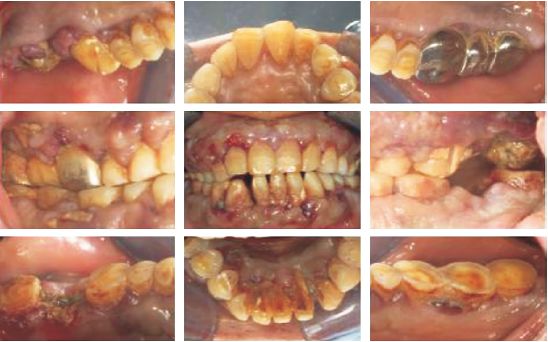

检查:血压106/71mmHg;全口牙龈肿胀且增生明显,呈苍白色,可见明显的出血斑点和坏死;软垢(++),龈上牙石(++),PD(-),BOP(+);31、41、48松动Ⅲ°,12、15、16、32、37、38、43~46松动Ⅱ°,11、13、14、21~25、36松动Ⅰ°;26~28固定义齿修复,边缘及咬合接触不良;17、47见拔牙创,愈合状况不佳(图3)。

图3  病例2患者口内相